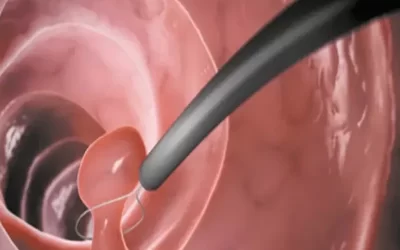

درمان ناباروری با هیستروسکوپی

در صورتیکه قاعدگی به همراه خونریزی شدید دارید، احساس گرفتگی در ناحیه شکم می کنید و یا پزشک متخصص شما نیاز به بررسی های بیش تری در خصوص وضعیت سلامتی شما دارد، ممکن است هیستروسکوپی را برایتان تجویز نماید. این پروسه به وی اجازه می دهد تا رحم و دهانه...